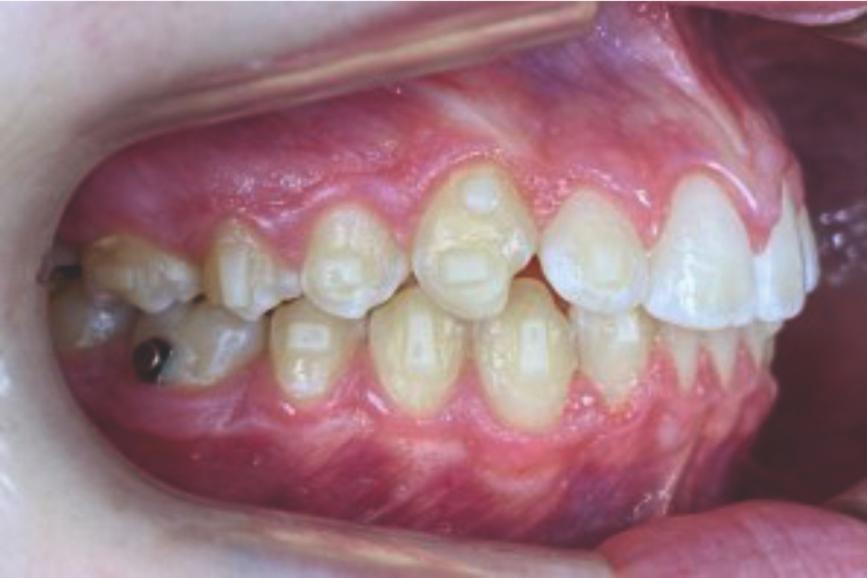

Chief complaint: We present the case of a 12-year-old female patient who came for an orthodontic evaluation, motivated by a family history of treatment. Clinical and radiographic analysis revealed a skeletal Class II malocclusion with molar and canine relationships also in Class II, moderate crowding in both arches, a deviation of the dental midline, and ectopic eruption of tooth 13. No functional issues with breathing or swallowing were observed, and oral health was generally good. A slight mandibular retrusion was noted in the soft tissue profile. A treatment plan was proposed using the Angel Aligner Pro system, aiming to correct dental misalignments and improve facial harmony through a minimally invasive, growth-adapted approach.

Clinical examination and diagnosis

- Woman ; 12/3 years

- Skeletal Class II

- Molar and canine Class II

- Upper and lower dentoalveolar compression

- Increased overjet and overbite

- Upper midline deviated 0,5 mm to the right

- Moderate upper and lower crowding